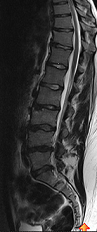

So ich häng euch mal noch mein nettes MRT Bildchen an, damit ihr noch was zum schauen habt (-; und sich der Text evtl nicht ganz so trocken liest.